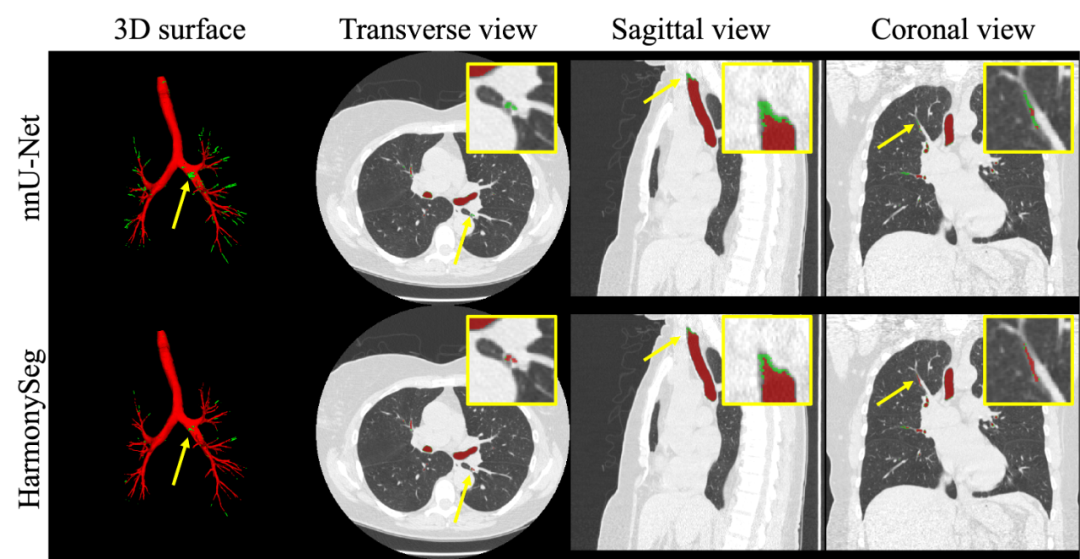

图4. 肝脏血管分割结果示例。红色表示分割结果,绿色表示对应标签。黄色箭头突出改进之处。

图6. 气管树分割结果示例。

在HVS任务中,HarmonySeg在衡量分割整体性能的Dice和血管树连通性的clDice上都实现了最优的性能,F1-score的优化也表明HarmonySeg在recall和precision之间实现了有效的平衡。其他任务中HarmonySeg也表现良好。整体来看,HarmonySeg在上述任务中均表现出了具有竞争力的性能,在多项指标上领先于已有模型。